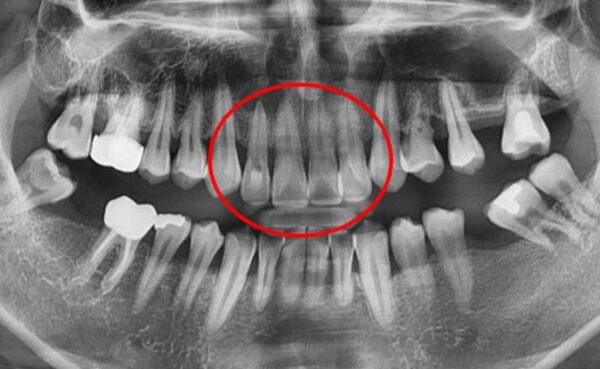

이미지 위에 가운데 동그라미를 클릭한 상태에서 왼쪽 또는 오른쪽으로 드래그해보세요! 드래그할 때마다 환자의 전후 변화를 확인하실 수 있습니다.

#자연치아보존 치근단절제술 환자 사례 : 드림연합치과 치근단절제술 사례 전후